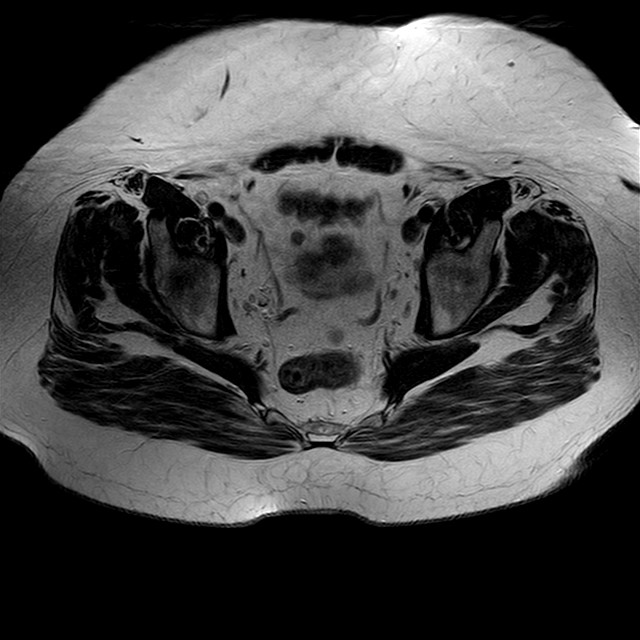

Esami: RMN BACINO

eT2w TSE

Evidenti e simmetriche alterazioni osteofitosiche in regione coxo femorale con riduzione delle rime articolari. Degenerazione completa del cercine glenoideo. Non attuali segni di versamento articolare. Non segni di edema osseo che escludono attuale algodistrofia od osteonecrosi. Lieve e simmetrica riduzione del trofismo della muscolatura glutea.